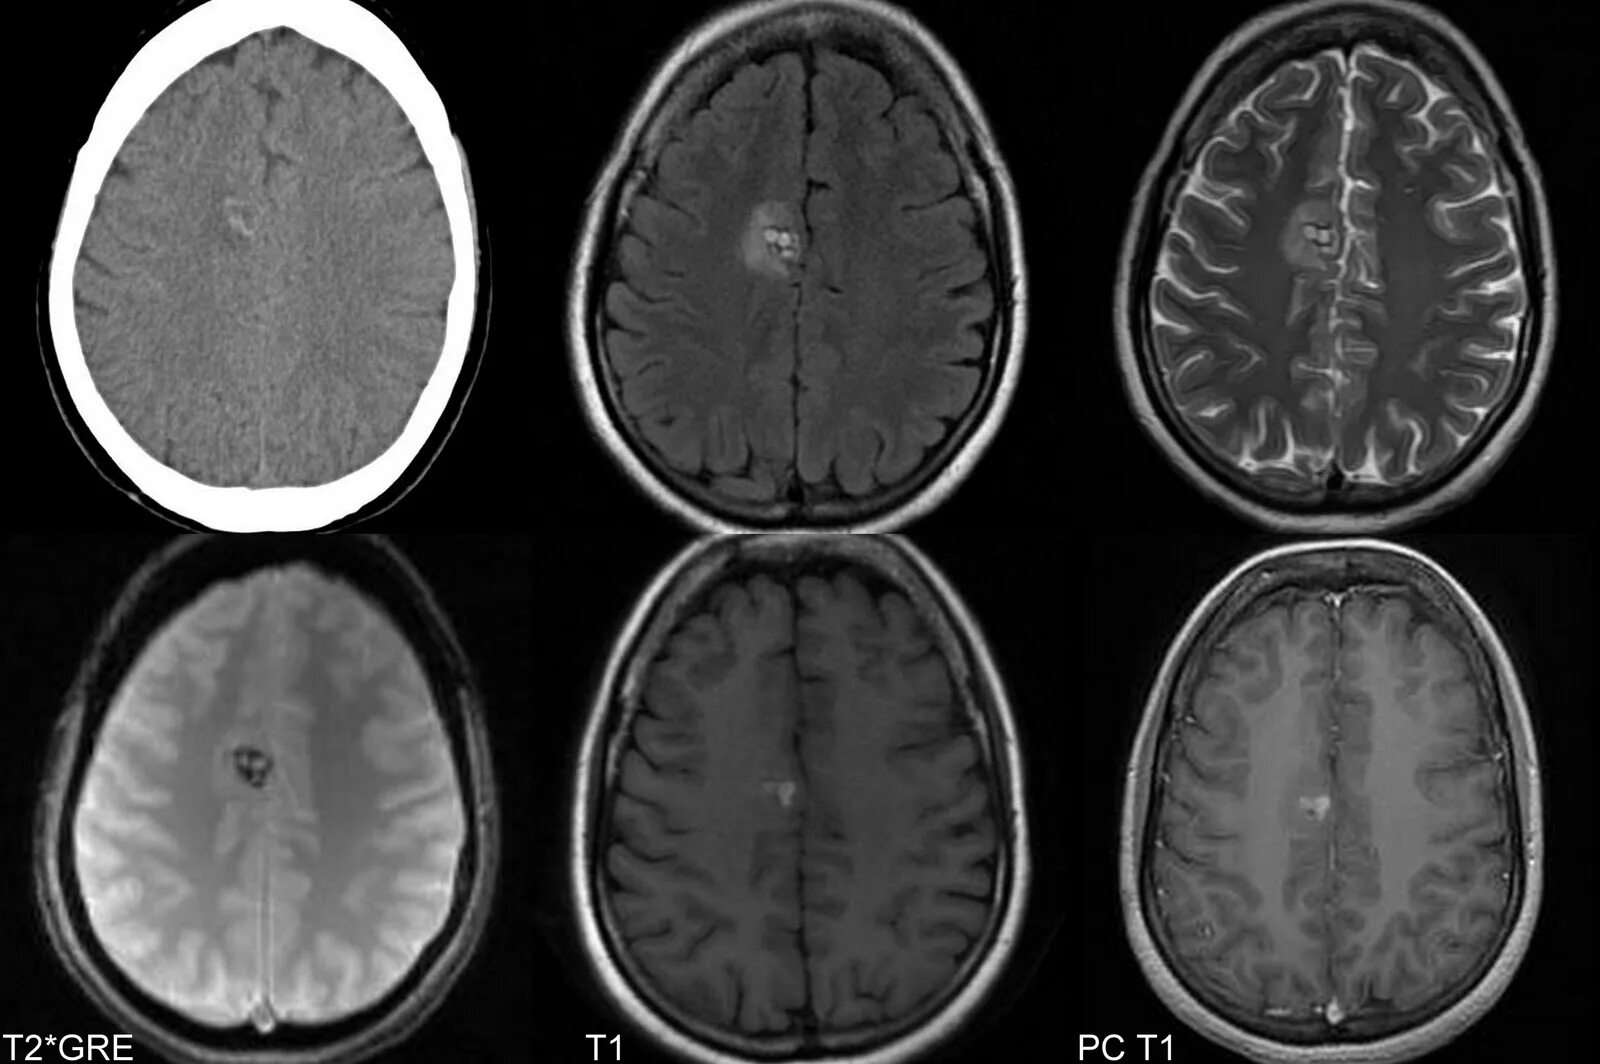

Очаг глиоза в теменной доле